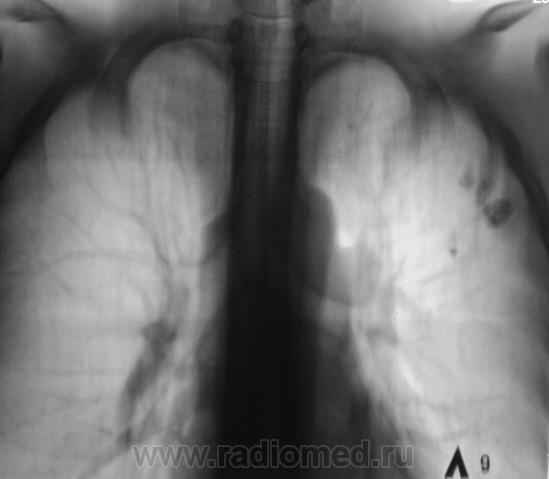

Пациент прооперирован - лобъектомия.

После операции.